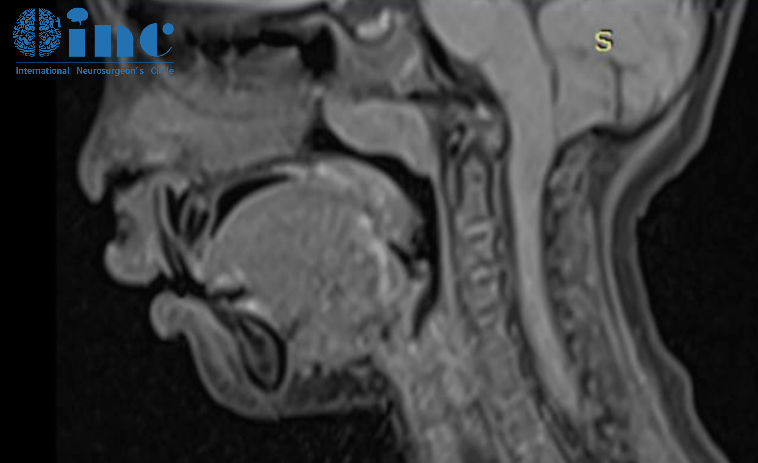

2022年1月初进行的全脑和脊髓MRI检查显示小脑蚓部和扁桃体疝以及脊髓空洞腔,从C4到T11更明显(但也涉及到了脊髓的较尾部),没有任何明显的脊髓栓系的证据。

小脑结构的下降几乎完全闭塞了脑池的空间,明显干扰颅脊交界处的脑脊液循环。

CT重建提示颅脑比例失调,这是因为大脑凸面的蛛网膜下腔体积减小,小脑蚓部向上迁移,以及与小脑中度过度生长相关的小脑幕的向上移位。

即使涛涛的临床状况有所好转,并且他没有抱怨头痛或其他症状,也应该考虑手术矫正I型小脑扁桃体异常。由于颅底脑脊液循环的障碍,脊髓空洞症很可能从其已经很长的范围发展到全脊髓空洞症。

考虑到目前良好的神经系统状况,我会选择枕下中线开颅术和Cl后弓切除术。在我们的大多数病例中,这种手术足以控制病情,甚至从长远来看(手术矫正后几个月)脊髓空洞症得到消退。